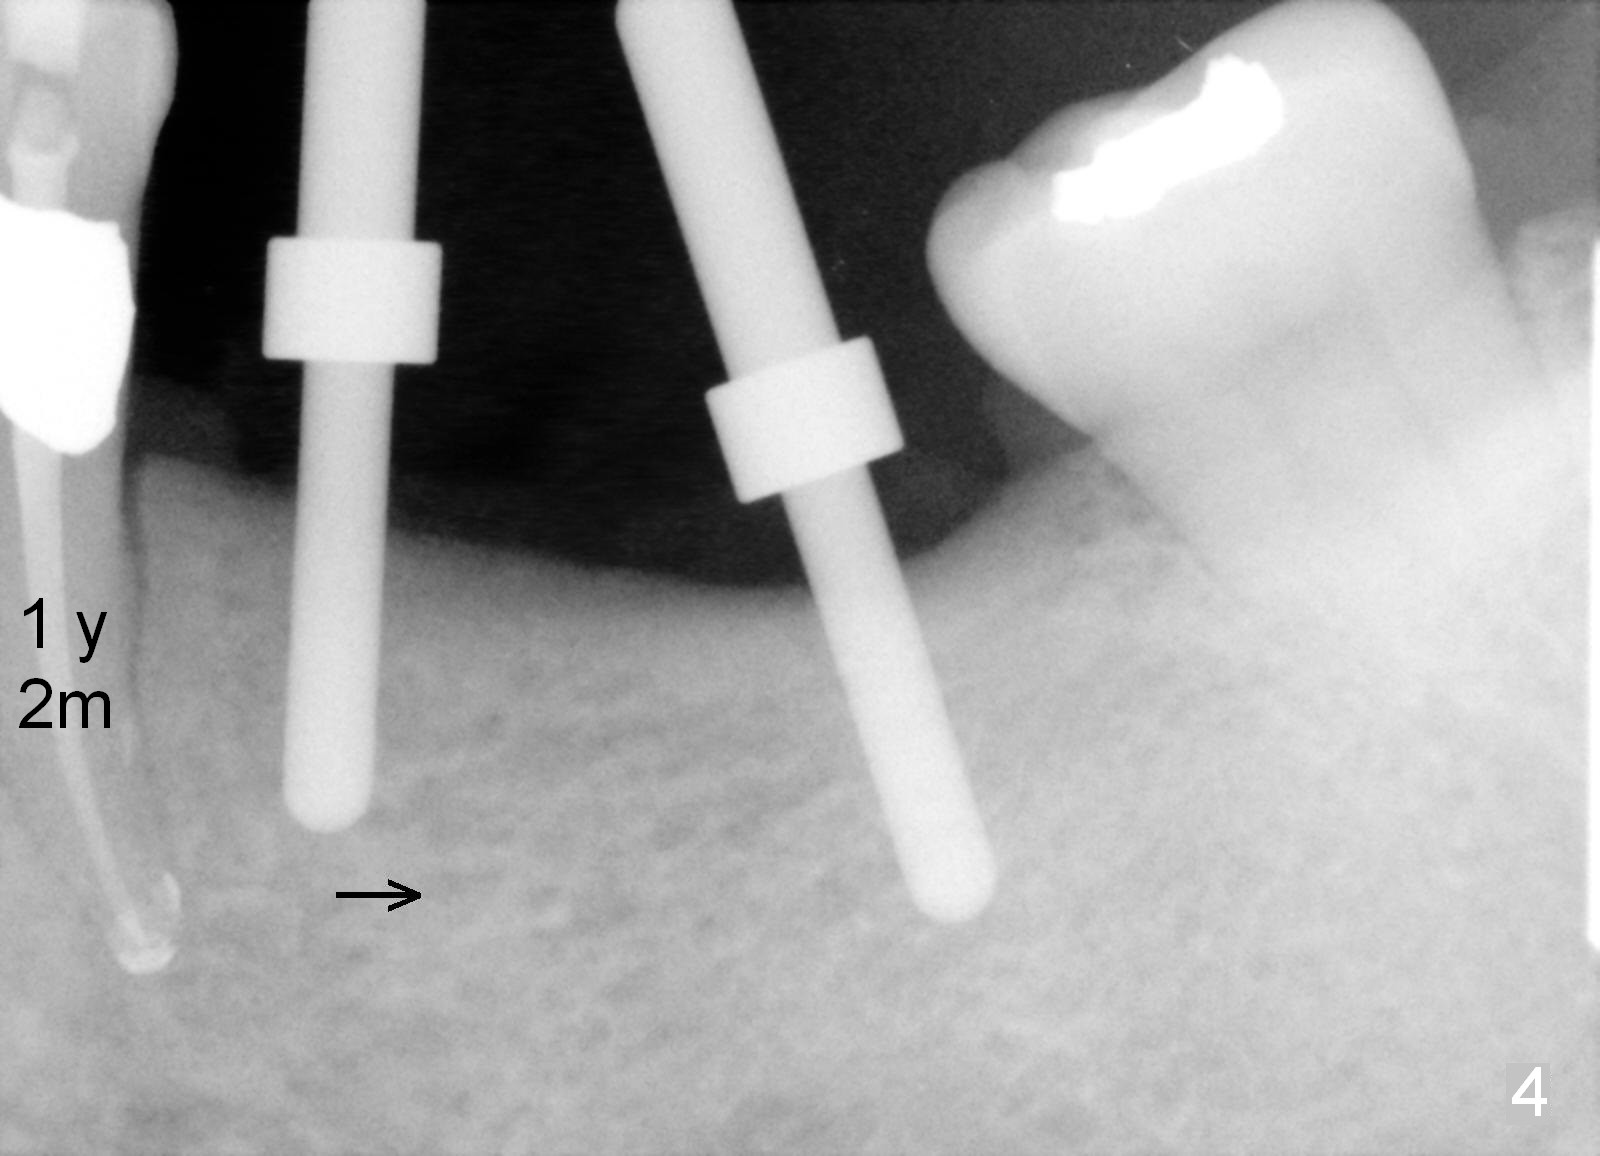

One year 2 months post root canal therapy at #20 (Fig.4), osteotomies are initiated at #18 and 19.  The trajectory at #19 is subsequently corrected (Fig.5); that of #18 should be also corrected (arrow).  The fact of the narrow ridge (Fig.6) is also ignored intraop.  Without further adjustment, the osteotomies are enlarged (Fig.7) and the implants are placed (Fig.8: 4.5x14, 5x14 mm).  As expected, the buccal coronal implant surface is exposed.  The buccal plate is decorticated with placement of autogenous bone graft.  Periodontal dressing is applied.  Postop, the wound is infected with wound gapping.  With irrigation, the wound finally heals.